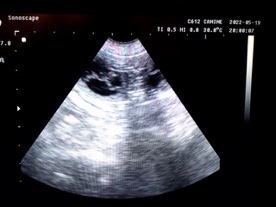

Marec 2022 - podávame Acidum Folicum,